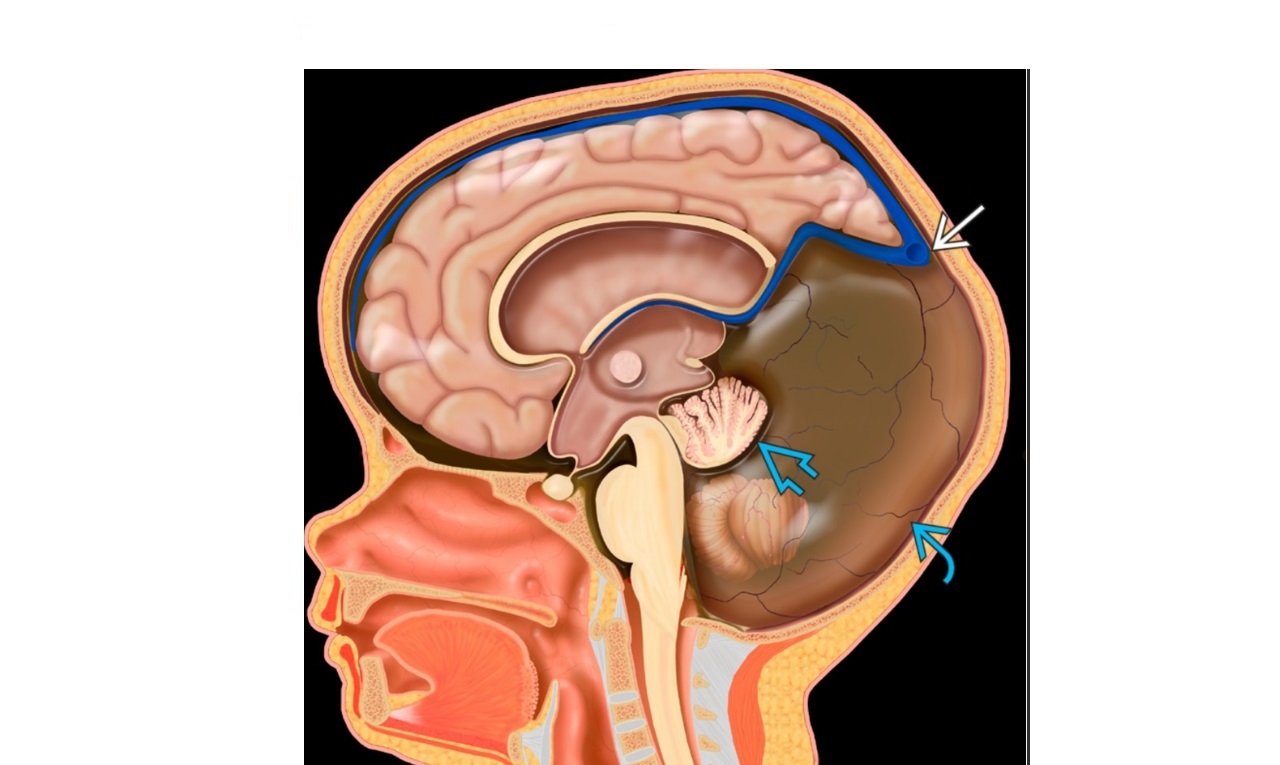

60

= **Small posterior fossa with cerebellar compression and hindbrain herniation through foramen magnum ** -cerebellar herniation -4th ventricle compression = hydrocephalus -obliteration of the cisterna magna ***-lumbar myelomengiocele*** Other findings include ***callosal dysgenesis*** tectal beaking enlarged massa intermedia cervical medullary spUR Foetal US -Banana sign if cerebellum wraps around midbrain -Frontal bone concavity (lemon sign) CT and MRI -colpocephaly (enlarged occipital horn and atria) ‘batwing’ configuration of frontal horns on coronal view (pointing inferiorly secondary to enlarged caudate nucleus), -‘hourglass ventricle’ - excessive cortical gyration (stenogyria)